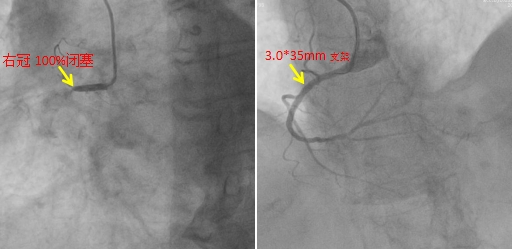

从患者12:48到达导管室,到13:07导丝顺利通过,支架植入,血管疏通,用时仅仅19分钟!整个过程可谓争分夺秒!